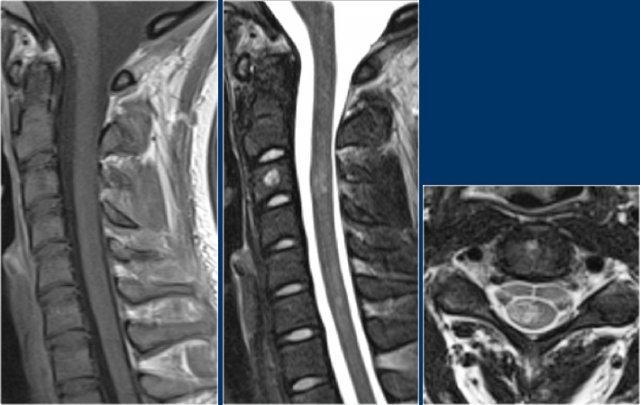

Rò động tĩnh mạch (AVF) cột sống

Dị dạng mạch máu phổ biến nhất của tủy sống là rò động tĩnh mạch màng cứng (dural AV-fistula).

Bệnh lý này bao gồm một kết nối bất thường giữa động mạch và tĩnh mạch, có thể dẫn đến tăng áp lực tĩnh mạch, tạo điều kiện cho tủy sống bị thiếu máu cục bộ và ít phổ biến hơn là xuất huyết.

Rò động tĩnh mạch (AVF) thường gặp ở người cao tuổi và được cho là hậu quả của chấn thương.

Chẩn đoán chính xác rất quan trọng vì các tổn thương này có thể là nguyên nhân gây bệnh tủy sống có thể hồi phục được.

Lưu ý vùng tăng tín hiệu ở đoạn tủy ngực dưới và các mạch máu giãn xung quanh trên chuỗi xung T2W.

Trên chuỗi xung T1W có tiêm thuốc tương phản từ, có hiện tượng ngấm thuốc nhẹ.

Một trường hợp khác với bệnh tủy sống và giãn tĩnh mạch là hậu quả của rò động tĩnh mạch (AVF).

Một bệnh nhân khác với bệnh tủy sống và các mạch máu giãn bao quanh tủy.

Lưu ý các vùng giảm tín hiệu trên chuỗi xung T2W, biểu hiện của xuất huyết.

Một trường hợp rò động tĩnh mạch (AVF) khác với bệnh tủy sống và giãn mạch máu.